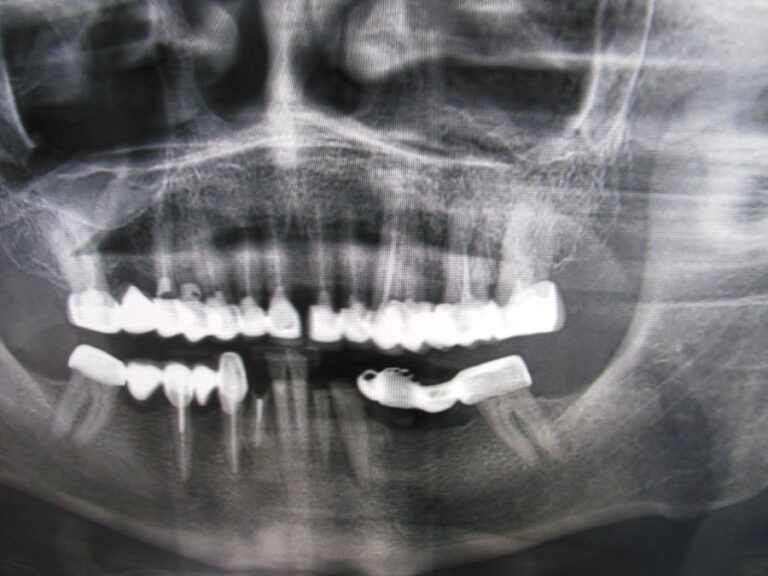

Implanty zygomatyczne

Przykłady implantologii